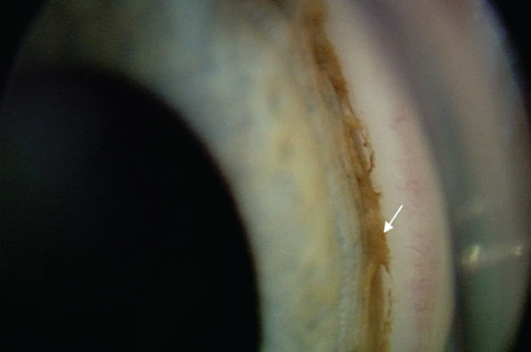

Установлено, что варианты гониодисгенеза у больных с глаукомой на фоне рубцовой РН, выявленные при иридокорнеальной гониографии, зависели от степени её выраженности. При 1-й степени в основном преобладали признаки дисгенеза УПК в виде гребенчатых связок — 2 глаза (22,2 %) и переднего прикрепления радужки — 4 глаза (44,5 %), при 2-й степени чаще встречалось изолированное переднее прикрепление радужки — 16 глаз (28,6 %) или сочетание переднего прикрепления с остатками мезодермальной ткани — 35 глаз (62,5 %) (рис. 4, 5).

Рис. 5. Изображение угла передней камеры глаза ребёнка, 6 лет, с рубцовой ретинопатией 2-й степени, глаукомой (стрелкой показаны остатки мезодермальной ткани)

Fig. 5. Image of the anterior chamber angle of the eye of a 5 y.o. child with degree 2 cicatrical ROP and glaucoma (the arrow shows mesodermal tissue remnants)